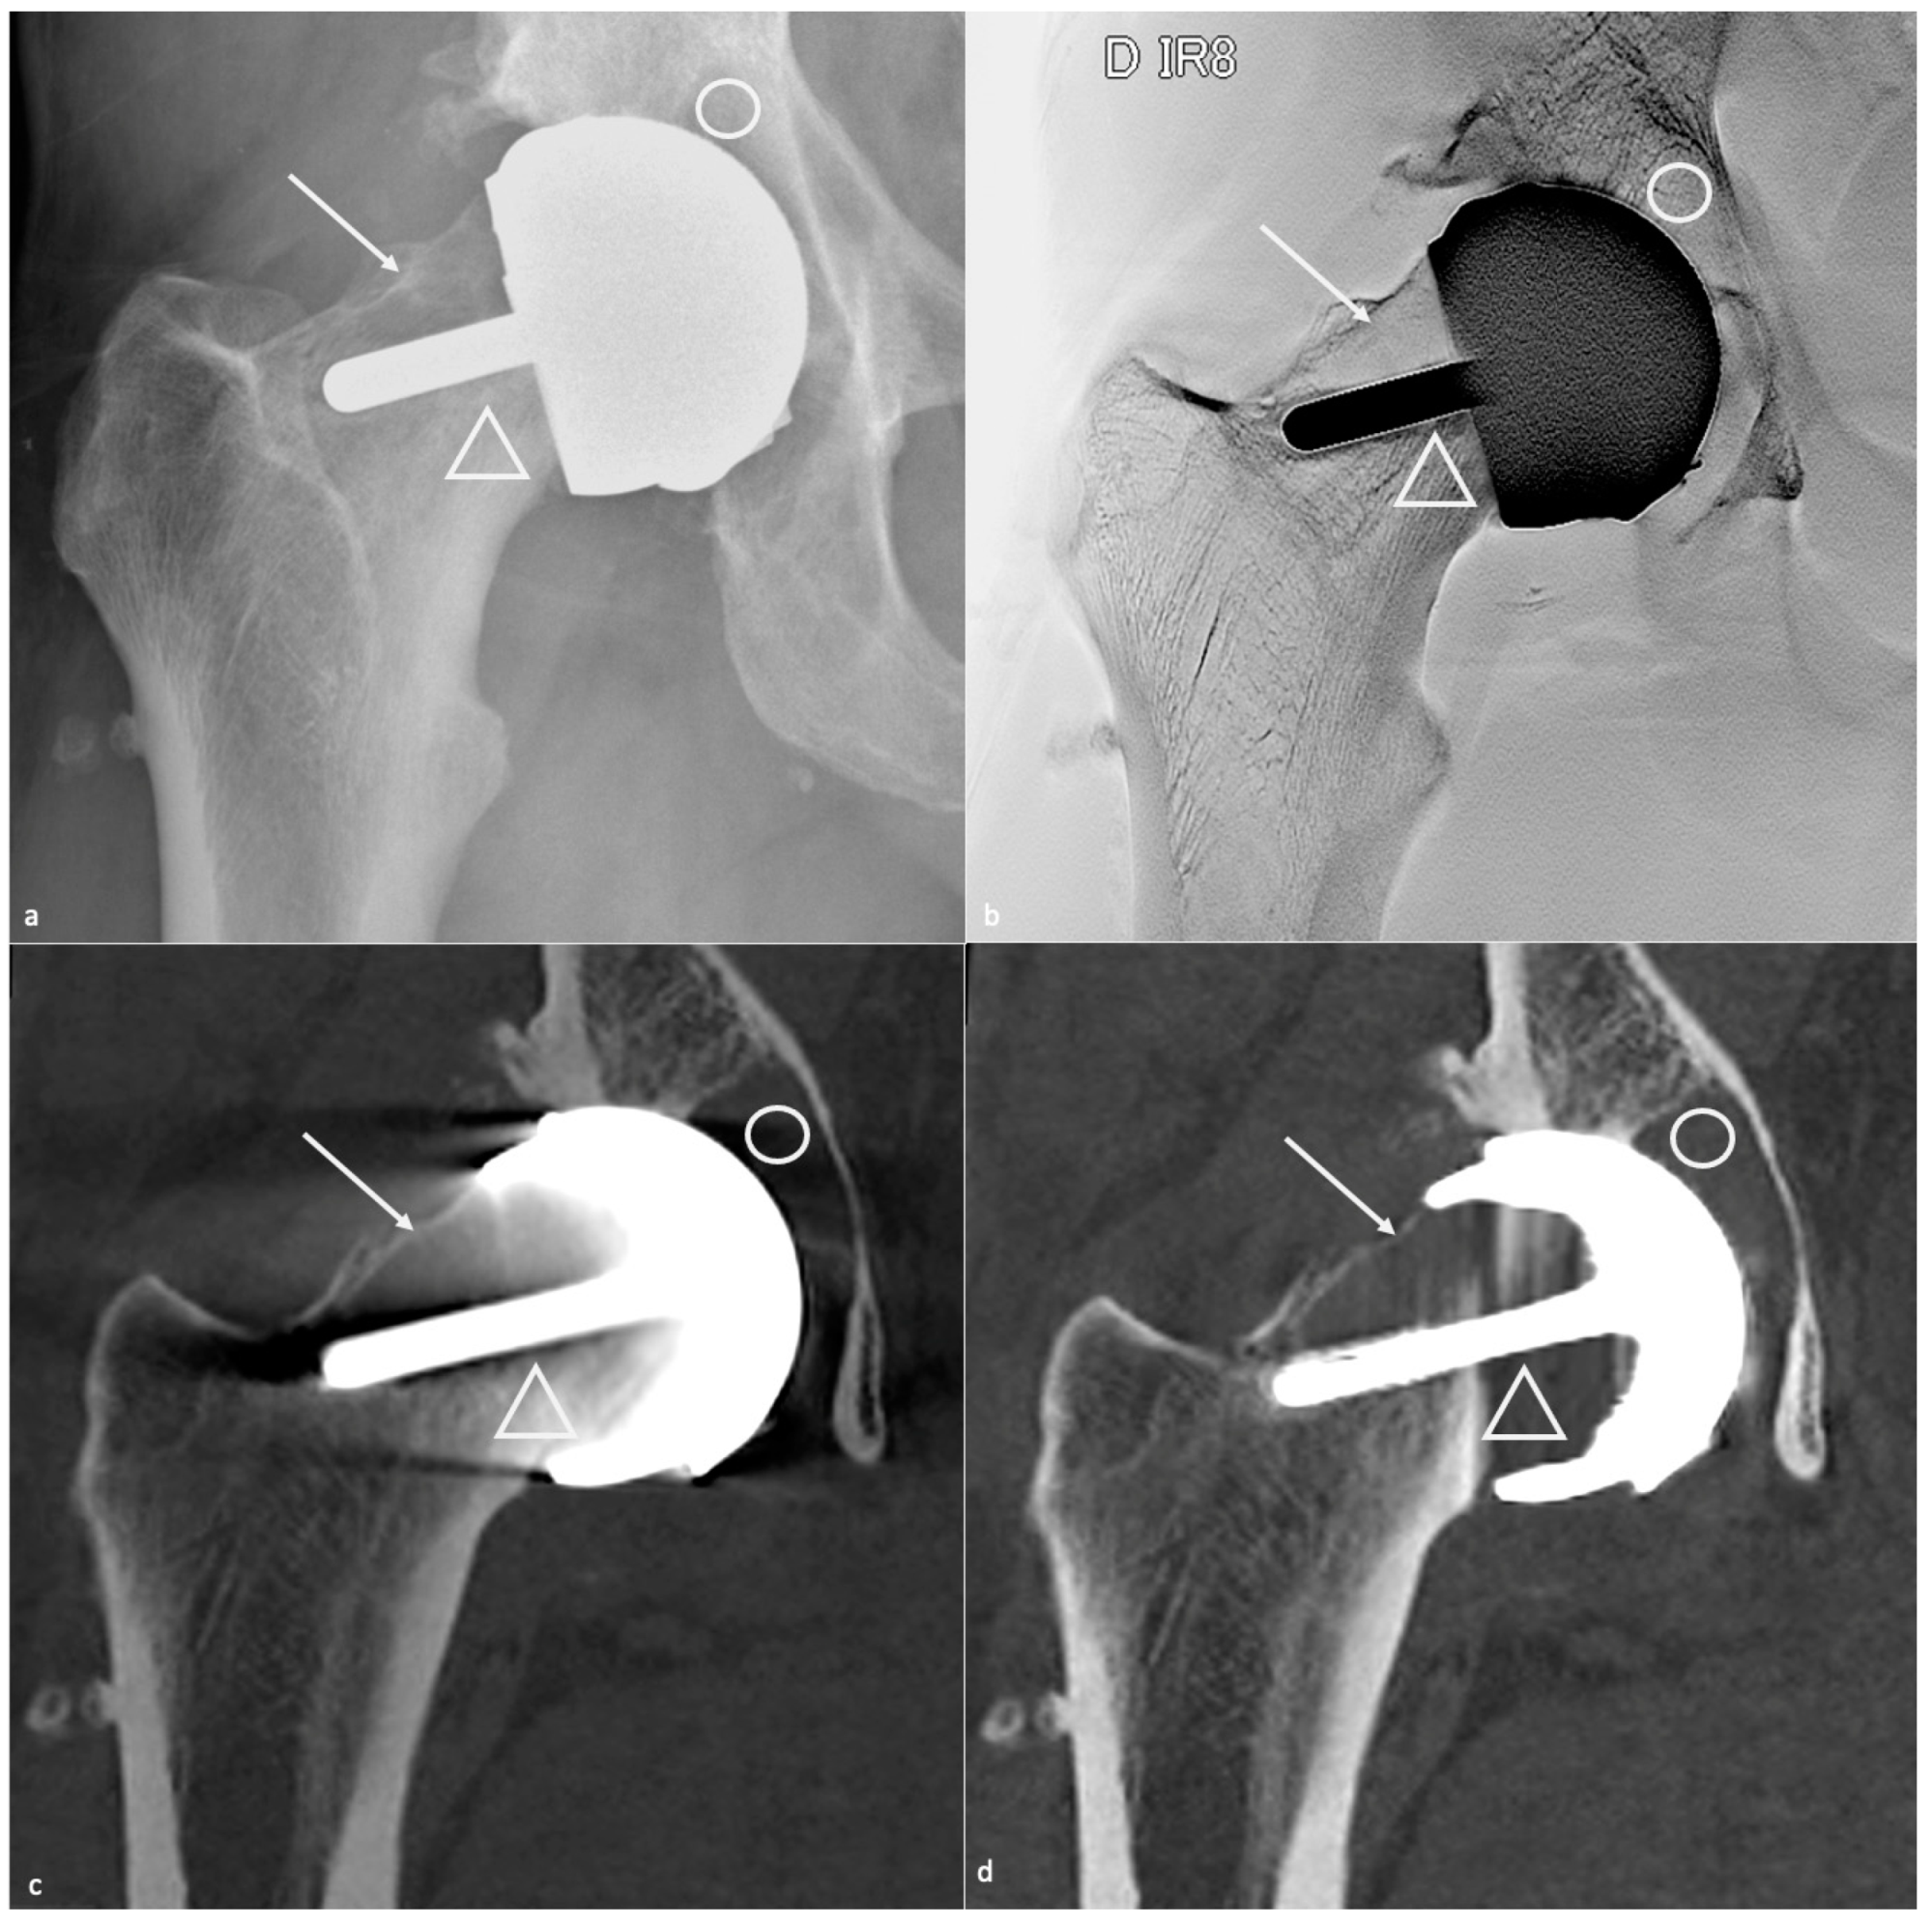

4.5.2. Classification and Contribution of Imaging Methods

- Metallosis results from the shedding of metallic debris (secondary to a MoM prosthesis with corrosion, a conflict between a metallic acetabular cup and the prosthetic neck, or a contact between a metallic head and an acetabular metal back in case of PE wear or dislocation) that induces synovitis and an indolent pattern of osteolysis, potentially leading to loosening (i.e., potentially looking similar to osteolysis and PE wear). Synovitis may contain low-signal intensity or metallic density debris, causing MRI artifacts and bone erosion, best depicted on CT-MAR (Figure 20). Such debris might also be located in periprosthetic soft tissue and lymph nodes [54,57]. Metallic debris presence might also accentuate PE wear (i.e., third fragment wear) [54]. Of note, high serum metal-ion levels can be found in symptomatic and asymptomatic patients and would be associated with pseudo-tumors, so that such a biological finding should lead to the prescription of an MRI to rule out a pseudo-tumor even in asymptomatic patients [6,103].

- Additionally, referred to as trunnionosis, trunnion corrosion corresponds to a soft-tissue reaction to metal debris released from micromotion and mechanical wear at the head–neck or neck–stem junction of modular MoP HA. On MRI, it manifests as an adverse local reaction associated with medial calcar resorption [11,104].